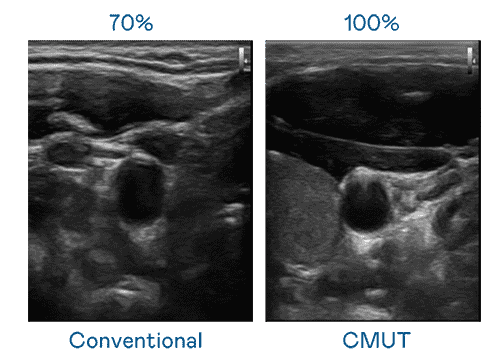

CMUT 技术是一种用电容式微机电元件来产生超音波讯号的技术。。。。与传统 PZT 压电式技术相比,,,,CMUT 频宽增加 30%,,更宽频的超音波讯号让影像解析度大幅提升,,,是实现高影像品质医疗超音波扫描、、促进精准医疗发展的关键技术。。。

大频宽带来超清晰影像

超音波影像的解析度高低,,首先取决于探头能发出的讯号频宽。。。918.COM CMUT 可提供高清晰的超音波讯号,,,,提供高频宽、、、高灵敏度、、、、影像纹理细节更高的超音波影像,,协助医护人员缩短影像判读时间及利用精准的医疗影像进行诊断。。。。